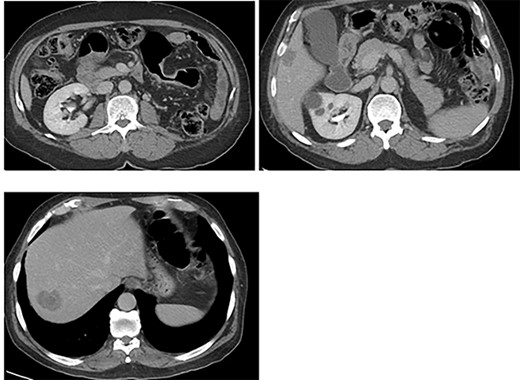

An otherwise healthy 73-year-old male, presented with rectal bleeding 6 months back. Colonoscopy revealed a sigmoid colon mass about 25 cm from the anal verge extending 10 cm proximally and a biopsy confirmed invasive adenocarcinoma (Fig. 1) Computed tomography of the abdomen and pelvis revealed a circumferential wall thickening involving the distal colon/proximal sigmoid colon spanning for 6 cm with maximum thickness of 2.3 cm, and it was also associated with surrounding fat stranding and multiple regional lymph nodes. Liver lesions were described as ill-defined hypodense lesions in two segments. The first lesion was seen in segment 7 measuring 6 × 7.5 cm and the other was seen in segment 5 measuring 6 × 3 cm (Fig. 2). Furthermore, chest CT showed no lung metastasis and a carcinoembryonic antigen level of 24.8. Eventually, a diagnosis of metastatic sigmoid adenocarcinoma with liver lesions was made. The multidisciplinary team decided to start the patient on Nac and then the case was reassessed for further resection. After completing five cycles FOLFOX, a CT of chest, abdomen and pelvis was performed for evaluating the response. The primary descending colon tumor demonstrated reduction in bulk with persistent serosal irregularity and no definitive regional lymphadenopathy was detected. The hepatic lesions revealed a partial response; in segment 7, the lesion is currently measuring 3.9 cm and in segment 5, the lesion measures 2.7 cm. Partial response to therapy was noted by a 41% reduction in sum tumor burden as per RECIST criteria (Fig. 3). The clinical tumor node metastasis classification post chemo was calculated to be T2N0M1 for descending colon cancer along with a CEA of <1.7. Despite not adding a biological agent with the systemic therapy which is the standard protocol in metastatic CRC, the patient achieved a remarkable reduction in tumor burden. The patient underwent a laparotomy with a low anterior resection of the rectum and anastomosis, synchronous resection of segments 6 and 8 of the liver along with a right-sided diaphragmatic stripping.